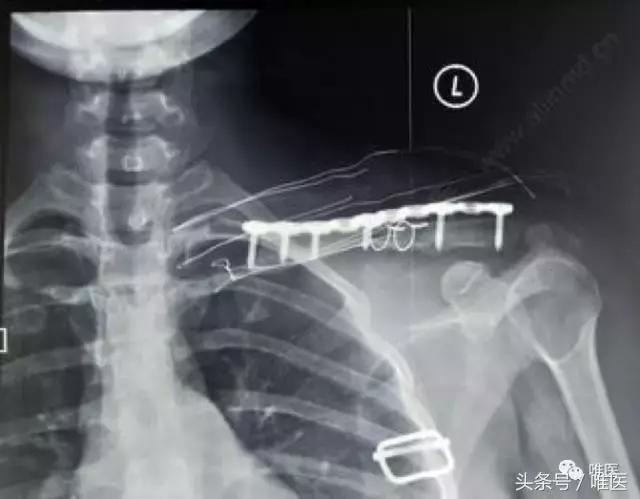

术后影像

锁定板及螺钉安放位置是否正确?

术中用钢丝*绑捆**是否合理?